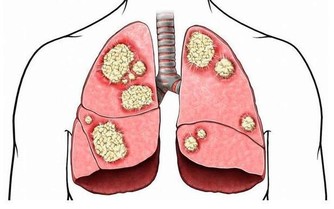

3患某種疾病導致的

如患系統性硬皮病,系統性紅斑狼瘡時頭髮不僅會變黃,還會大量脫落。